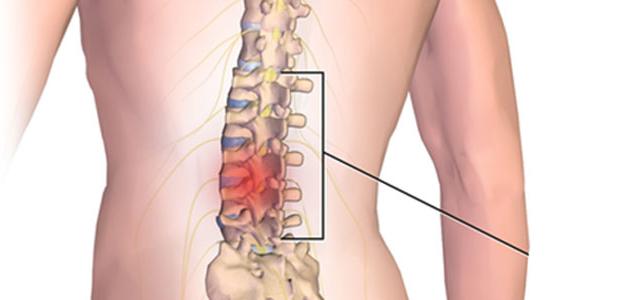

اعراض انزلاق غضروفي

هناك عدد من الأعراض التي ما إن تشعر بها حتى تدرك أن ما لديك هو ازلاقا غضروفيا.

يبدأ الألم في الظهر لأسباب عديدة، مثل ارتداء الكعب العالي من قبل النساء، أو تناول الغذاء بنظام غذائي سيئ، بالإضافة إلى ألم الظهر بسبب عدم علاج الديسك بالليزر في تركيا أو الانزلاق الغضروفي، حيث تعمل الديسكات المرنة بين فقرات الظهر على امتصاص الصدمات المختلفة التي يتعرض لها الجسم، ولكنها وفي بعض الأحيان قد تنزلق خارجة من مكانها أو قد تتمزق.

الألم

من أشهر اعراض الانزلاق الغضروفي البسيط وللأسف يبدأ الألم بطيئا ويتطور تدريجيا ليزداد سوءا مع مرور الوقت.

في بعض الحالات قد يمتد الألم ليشعر به المصاب في أقرب نقطة من الذراعين أو الرجلين إلى الغضروف المنزلق.

وخز وتنميل

إذا ما بدأ الغضروف المنزلق بالضغط على أحد الجذور العصبية، فمن الممكن أن يعيق عمل العصب في نقل الإشارات اللازمة إلى الأطراف، وهو من بوادر انزلاق غضروفي قوي. هذا الأمر قد يتسبب في شعور بالوخز والتنميل في اليدين أو القدمين أو الرأس.

ضعف عام في العضلات

قيتسبب هذا المرض في خلل بنقل الإشارات العصبية الضرورية إلى العضلات، فتجد ردود أفعالك بطيئة ولديك ضعفا عاما في عضلات الأطراف.

صعوبات عند محاولة الوقوف أو الجلوس : من الممكن للألم الذي يسببه الانزلاق الغضروفي أن يكون قويا وسيئا للغاية بالقدر الذي يمنعك من الجلوس أو الوقوف لفترات طويلة. حيث أن الوقوف والجلوس في هذه الحالة قد يتسبب في جعل الغضروف المنزلق يضغط بعد أكثر على الأعصاب في المنطقة المحيطة.

ألم حاد ومفاجئ عند القيام بحركات معينة

في بدايات الحالة، قد يشعر المريض بألم حاد ومفاجئ يباغته حال قيامه بحركات معينة، وذلك لأن الغضروف المنزلق يضغط بشكل بسيط على الأعصاب المحيطة عند الانحناء أو عند تحريك الجسم بطريقة معينة.

الشعور بالبرد في جانب واحد من الجسد

يتسبب ضغط الغضروف على أعصاب معينة محيطة بتطور شعور بطيء في الجسم، من الممكن وصفة بحرقة أو كالشعور بالتخدير أو حتى برودة تطال أحد جانبي الجسم فقط دون الآخر.

الشعور بالألم عند الضحك

فالمصاب بانزلاق غضروفي قد لا يتمكن من الاستمتاع بالضحك لما يسببه له من ألم قوي لضغطه على الظهر والغضروف المصاب.

ألم في الظهر عند العطس أو السعال

قد تتسبب أمور مثل العطس والسعال لدى المصاب بالضغط على منطقة البطن لديه، الأمر الذي قد يمتد للظهر ومنطقة الإصابة مسببا الشعور بالألم.